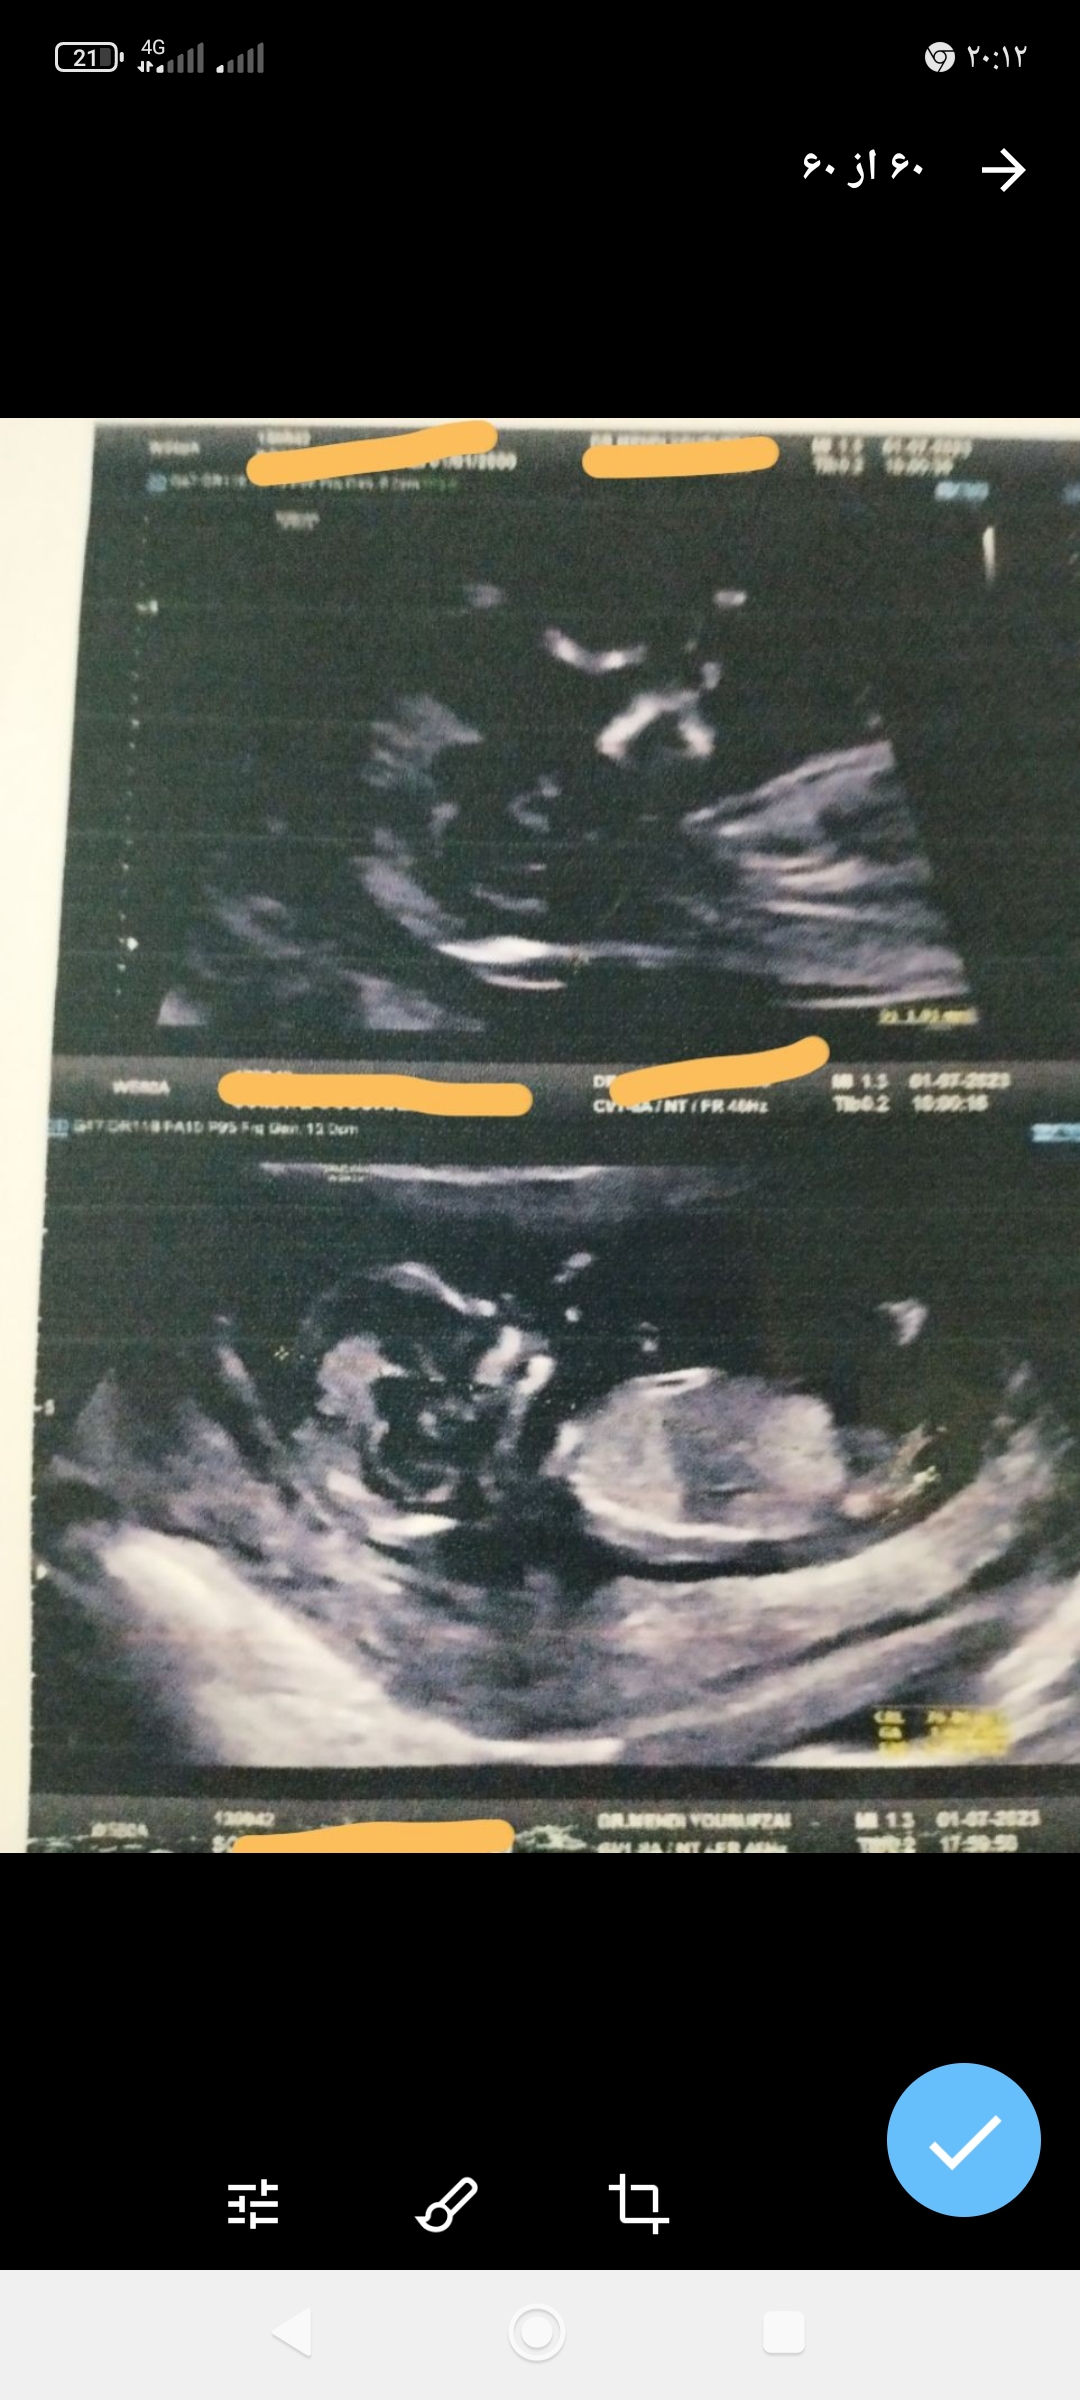

اول دختر دوم هم دخترررر😀😀😀 قسمت ما این بود خداروشکر میکنم